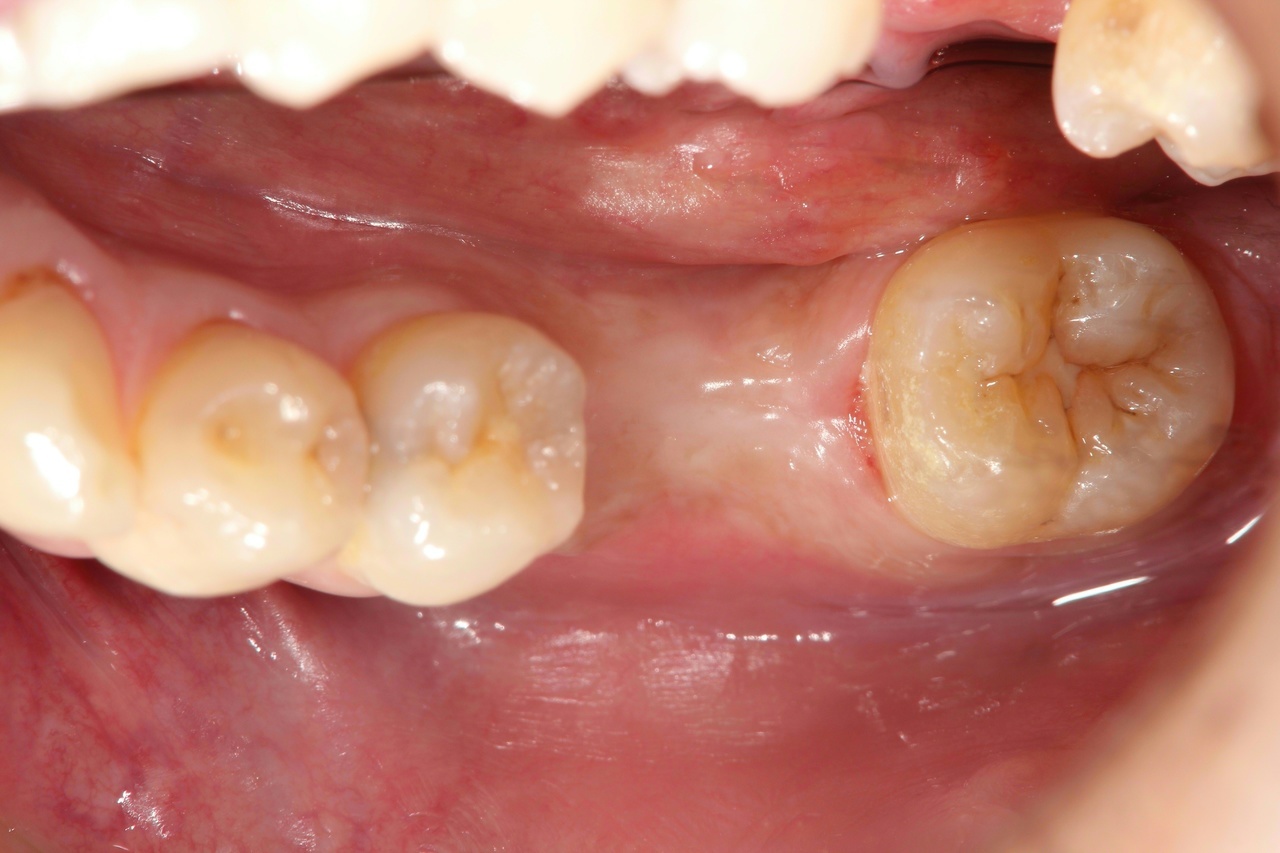

奥歯インプラント(スクリュー固定)

(伊東市 女性)

治療の流れ

むし歯で歯を失ってしまいました。

インプラントを埋入し、最終的な被せ物を装着しました。(ネジ穴をふさぐ前)

ネジ穴をふさぐとこの様な状態になります。